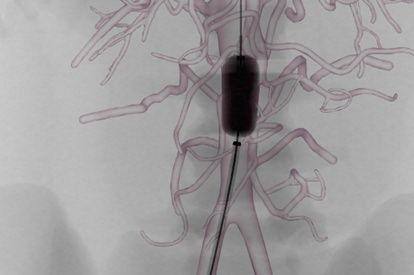

The ANGIO Mentor simulator is an essential tool for clinicians to practice and acquire the skills needed for performing endovascular interventions. Trusted by medical associations, hospitals, training centers, and the medical device industry globally, it provides trainees with realistic clinical settings to practice endovascular interventions using fluoroscopic and ultrasound guidance.

Offers true-to-life simulation of the clinical environment, including advanced imaging modalities like fluoroscopy/echocardiography, hemodynamic monitoring, medications, and interventional devices

TAVI (Transcatheter Aortic Valve Implantation) Module

Cardiac Rhythm Management (CRM) Module

Transseptal Puncture Module